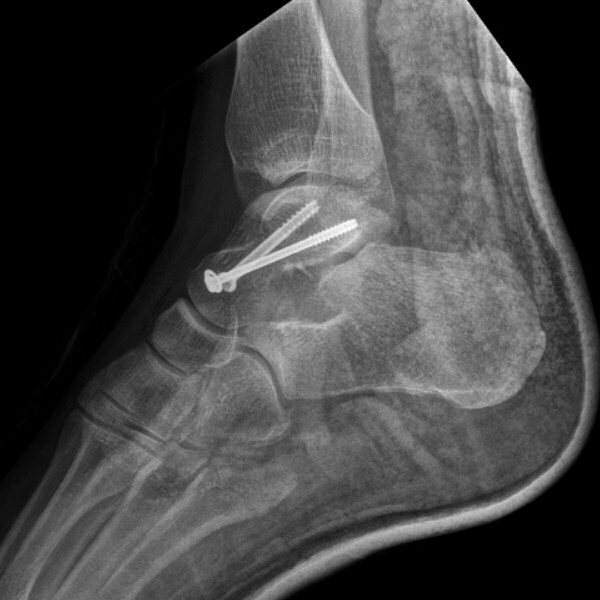

Talusfrakturen ovan fixerad med två skruvar

- Förbered snar operation med öppen reponering till exakt läge och skruvfixation med 2 skruvar, alt. 1 skruv och 1 stift.

- Vid helt odislocerad fraktur så kan man överväga perkutan stftning.